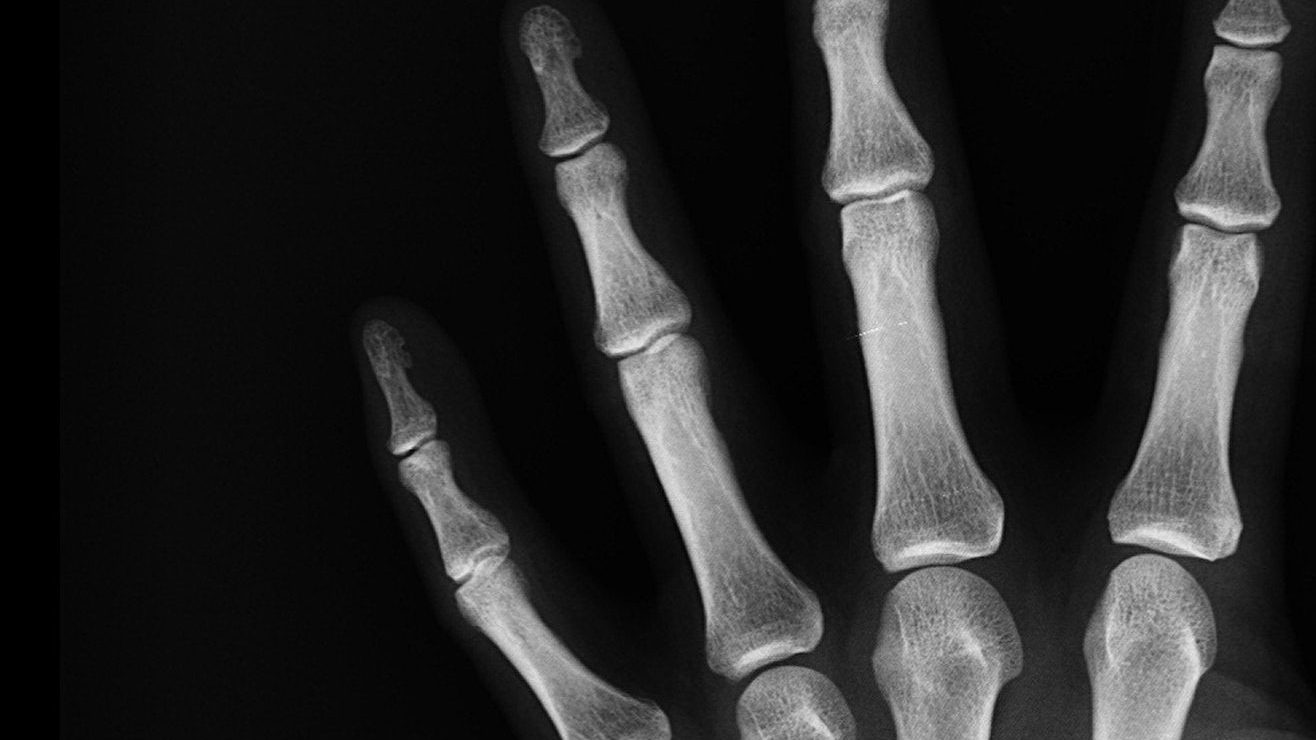

Levantar peso es fundamental para mantener la salud ósea. Crédito: Pixabay

Los huesos son mucho más que un simple andamio dentro de nuestro cuerpo. El hueso es un órgano complejo que viene en múltiples formas y tamaños.

Está conformado por una mezcla diversa de componentes orgánicos e inorgánicos, como colágeno y calcio.

Combinados, estos componentes crean una estructura lo suficientemente maleable como para que los músculos puedan tirar de ella para que podamos movernos, y al mismo tiempo son lo suficientemente fuertes como para proteger órganos críticos.

El hueso no es la estructura sólida, inamovible y permanente que muchos podrían suponer que es. El hueso vivo y sano permanece fuerte porque se renueva constantemente (el viejo hueso y dañado se va reemplazando con hueso fresco).